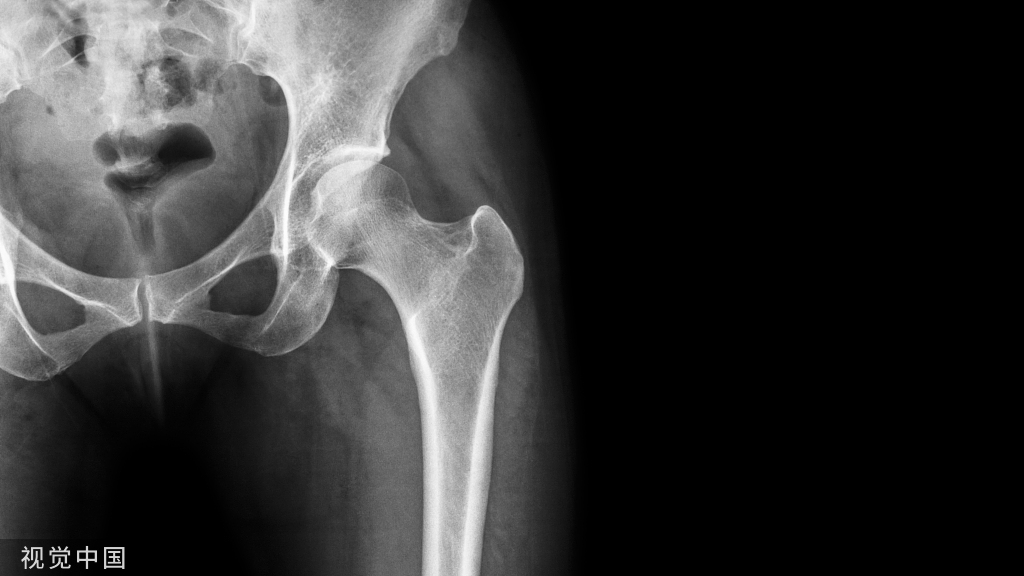

X线片的阳性改变较CT扫描还要延迟,多数病例X线片出现阳性改变在MRI确诊后的1年,少数患者可晚到2~3年,而且X线片的病灶显示均不清楚。因此,普通X线片对Ⅰ、Ⅱ期ONFH的诊断价值有限。但蛙式位X线片对显示新月征有其特殊价值。